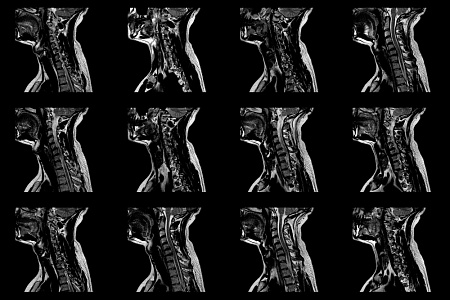

Нормальная и магнитно-резонансная анатомия позвоночника и спинного мозга |

Магнитно-резонансная диагностика дегенеративных изменений позвоночника |

Магнитно-резонансная диагностика инфекционных и воспалительных заболеваний позвоночника |

Магнитно-резонансная диагностика опухолей и опухолевидных заболеваний позвоночника и спинного мозга |

Магнитно-резонансная диагностика повреждений позвоночника и спинного мозга |